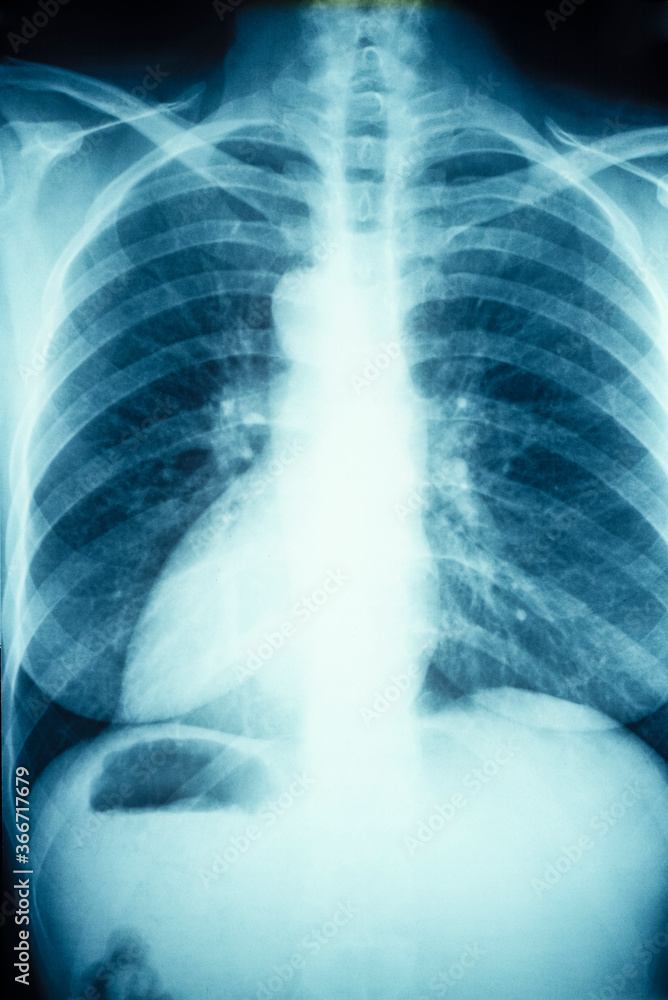

Chest X-rays Image Image & Photo (Free Trial) | Bigstock

www.bigstockphoto.comChest X-ray Image In Blue Tone Stock Photo | Adobe Stock

www.bigstockphoto.comChest X-ray Image In Blue Tone Stock Photo | Adobe Stock